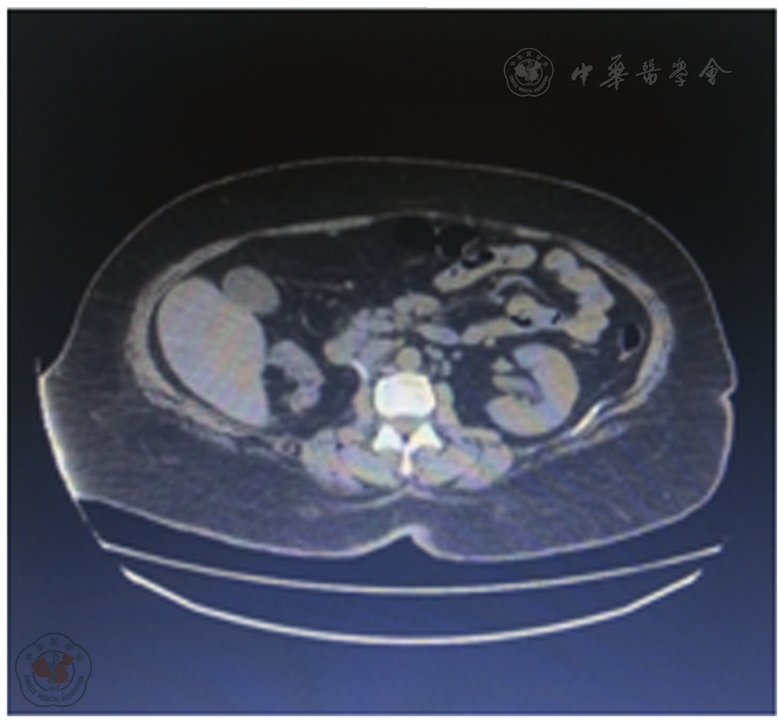

图2 2017年05月24日双肾CT